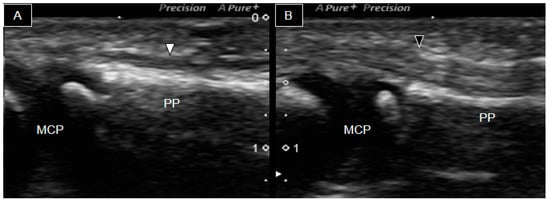

At the age of four, the patient presented to our clinic with restricted flexion movement in the right second and fifth fingers despite normal phalangeal bones. Fingers with hypoplastic bones displayed a decreased flexion ability. Ultrasound examination was conducted using a Canon Toshiba Xario 100S machine (Canon Medical Systems USA, Inc., Tustin, CA, USA) equipped with a 14L5 linear array. Figure 2 illustrates the longitudinal palmar view of the second fingers bilaterally. A thin, hyperechoic, fibrillar structure over the hyperechoic bony cortex (indicating the second flexor tendon) was observed. However, it was challenging to distinguish whether it was the flexor digitorum profundus (FDP) or superficialis (FDS). The ossifying epiphysis of the second metacarpal, proximal, and middle phalanges was yet not fused with the diaphysis. The right finger flexor tendon extended from the MCP joint to the PIP joint (Figure 2A). However, it became progressively thinner and more difficult to be traced, as it passed through the PIP joint, suggesting tendon hypoplasia without attachment to the middle phalanx. In contrast, the left flexor tendon was notably thicker (Figure 2B) and identifiable from the MCP joint to the distal middle phalanx area.

Figure 2. Ultrasound image of the palmar side of the second right (A) and left (B) fingers. The right flexor tendon (white arrowheads) was significantly thinner than the left one (black arrowheads) and was not visible over the right middle phalanx. MCP, metacarpophalangeal joint; PP, proximal phalanx; PIP, proximal phalangeal joint; MP, middle phalanx.